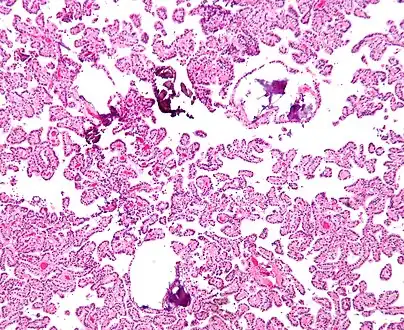

The tumor is neuroectodermal in origin and similar in structure to a normal choroid plexus. They may be created by epithelial cells of the choroid plexus.

Micrograph of a choroid plexus papilloma. H&E stain. -

Plexuspapillom Detail -

Plexuspapillom Overview